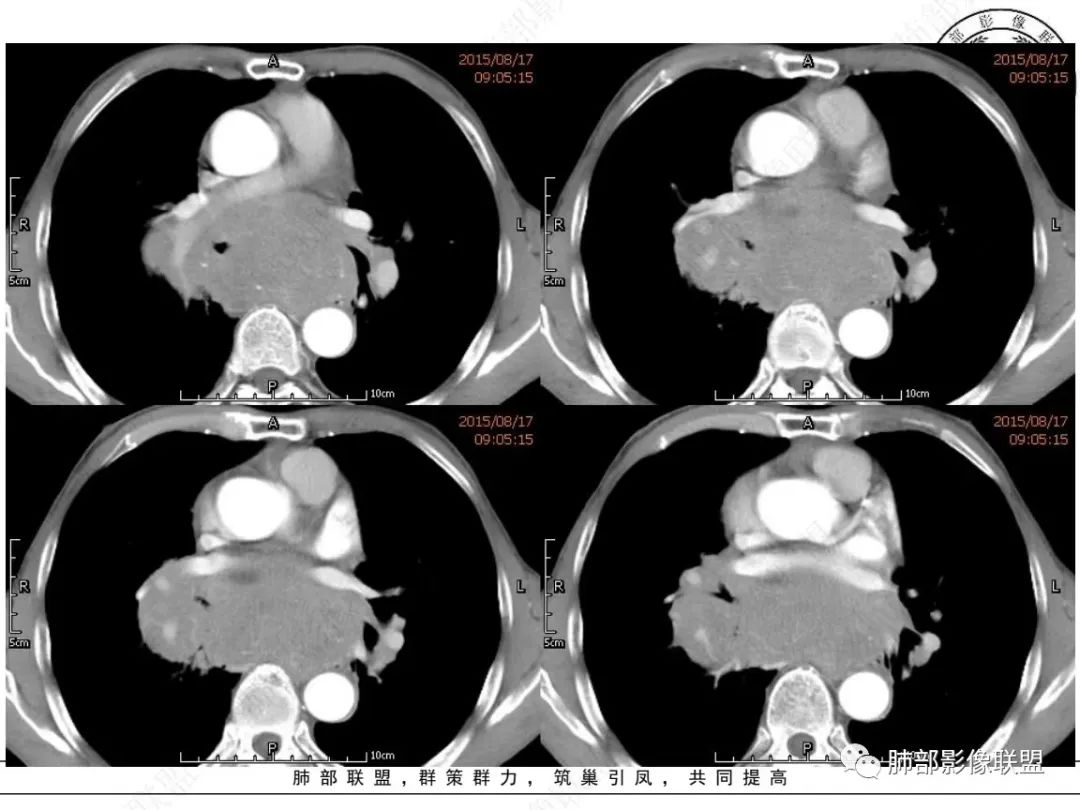

套细胞淋巴瘤( mantle cell lymphoma,MCL) 是一种伴有特征性的 t(11;14)( q13;q32) 易位的成熟B 细胞淋巴瘤,肿瘤细胞通常表达 cyclin D1、CD5 和SOX11[ 1-2] 。 占 非 霍 奇 金 淋 巴 瘤 ( non-Hodgkin lymphomas, NHL) 的 3 ~ 10%。

MCL是一种起源于淋巴结滤泡套区内的小B细胞,在2000年WHO分类中被作为一类独立的疾病而命名为MCL,既往文献报道。其特点为老年男性多见,就诊时多为疾病晚期,75%~100%表现为广泛淋巴结受侵,结外病变发生率较高。

MCL 好发于淋巴结,大多数患者就诊时临床分期为Ⅲ~ Ⅳ期,多伴有淋巴结外侵犯。 MCL是一种非常独特的病理类型,一方面按照其侵袭性的生物学行为和自然史应归为侵袭性NHL,而另一方面,它对治疗的反应类似惰性淋巴瘤(indolent lymphoma),采用目前的标准治疗方法是不可治愈的。常规治疗很难治愈, 患者的中位生存时间仅为 3 ~ 5 年,甚至有些复发难治患者总生存时间仅为1 ~ 2年 。

MCL的CT表现为分布无规律的全身多区域淋巴结受侵,少有单一区域淋巴结受累,结外器官受侵多见;MCL有一般NHL淋巴结受累基本CT表现,平扫CT表现为病变密度均匀,受累淋巴结区内呈融合状生长,边界清楚,增强后病灶呈均匀、中等强化,一般病变内无低密度坏死区。确诊需要病理及免疫组化,根据肿瘤组织形态学和免疫组织化学 CD5 及cyclin D1 的表达绝大多数 MCL 可做出明确病理诊。

1.小细胞肺CA:好发吸烟老年男性。常有血液NSE及胃泌素释放肽前体升高。Syn、CgA、CD56阳性。其CT特点可有:冰冻纵隔、冰冻肺门。血管包埋征。针尖样支气管。鸭蹼状凸起。娘小崽大。脂肪间隙消失(常指纵隔及肺门内)。阻塞性炎症不重。侵袭性强。破坏力不强。收缩力弱,内无空泡。沼泽样强化,坏死散而小,坏死不彻底,强化偏低。表面圆钝,角状及条状凸起,蠕虫样表现,腊肠样尾巴(朝肺门侧或背离肺门侧均可以)。胸水多“清澈”(可以理解为淋巴液回流障碍导致的胸水)。点簇状钙化(类似盐与胡椒样)。多见癌性淋巴管炎。另外黄勇老师提出胸膜下的小细胞肺癌具有“山丘征”的特点。